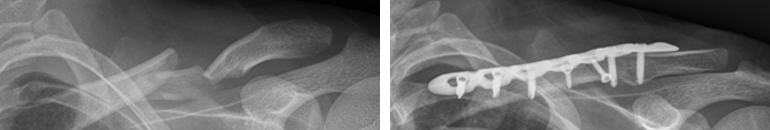

우측 쇄골의 중간(좌), 원위부(우)가 골절되어 어긋나 있습니다. 우측 쇄골의 중간(좌), 원위부(우)가 골절되어 어긋나 있습니다.

쇄골의 중간부위에 어긋난 골절을 금속판으로 고정한 수술 사진  쇄골의 중간부위에 어긋난 골절을 금속판으로 고정한 수술 사진